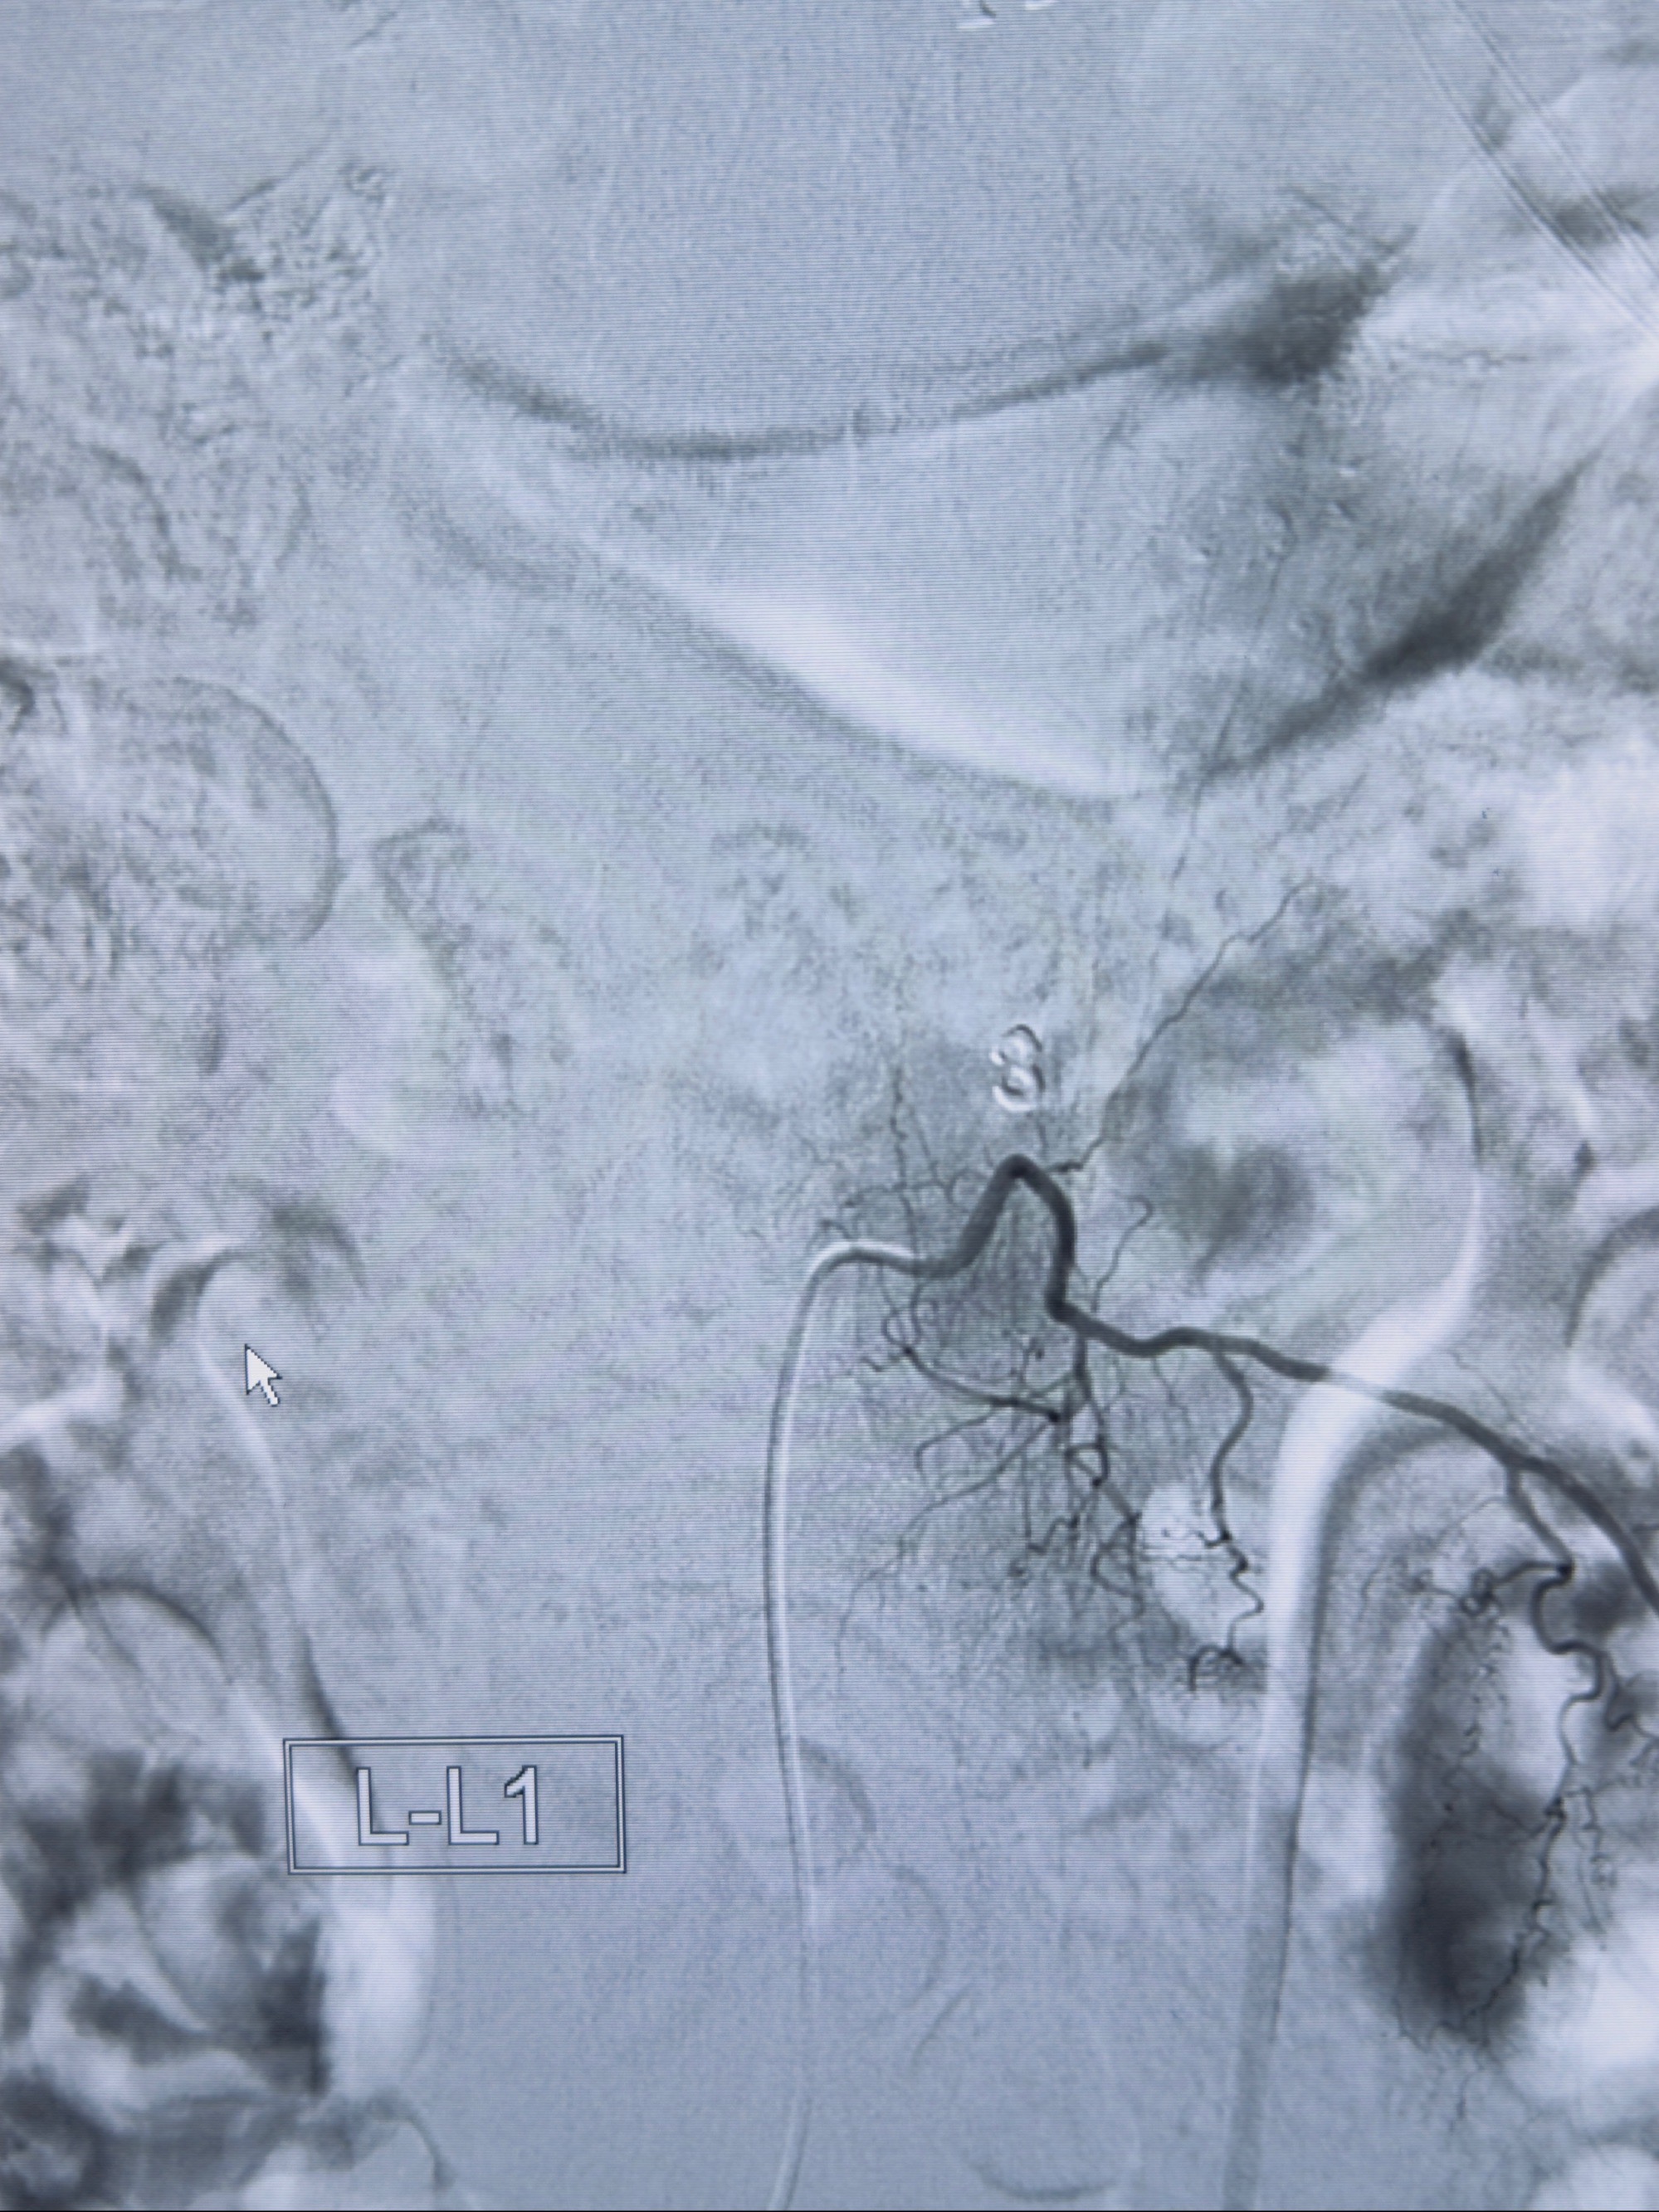

2023-10-13DSA:右侧L1水平硬脊膜动静脉瘘,供血动脉为右侧L1,附近动脉未见明确吻合供血,供血动脉处可见脊髓前动脉发出